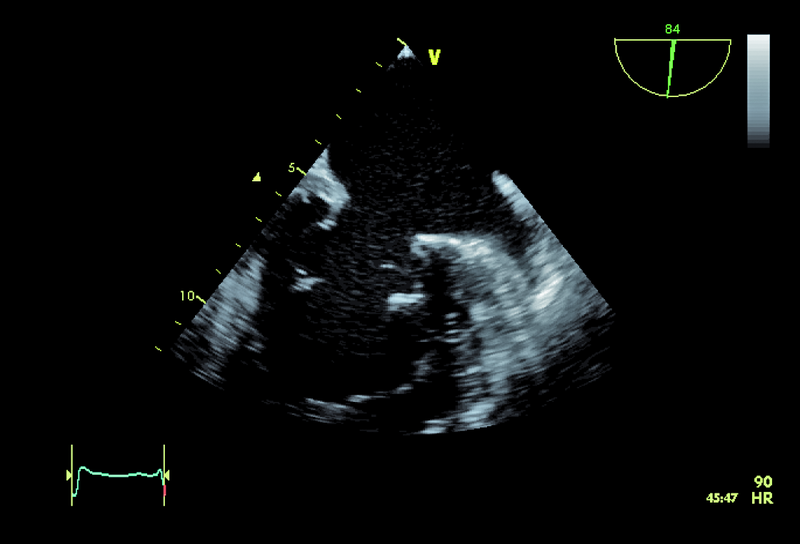

1. Zmiany degeneracyjne aparatu zastawki mitralnej (ryc. 1).